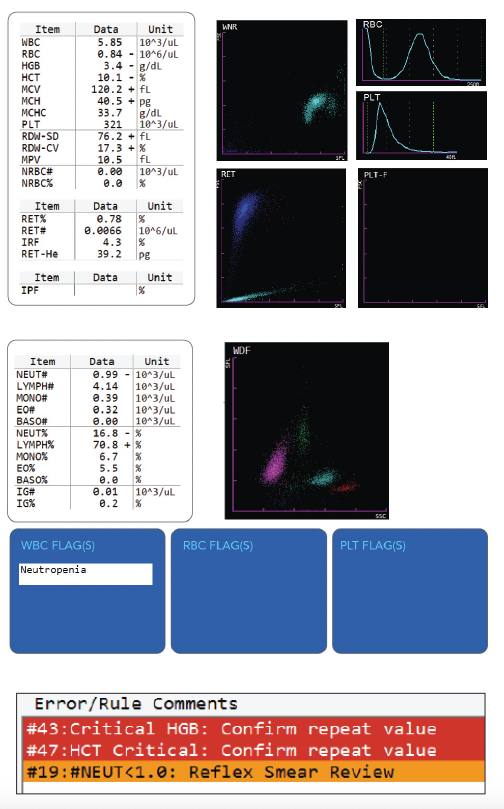

This sample (see PDF) was drawn from a 2 year old patient presenting to the pediatrician with pica (consumption of non-nutritive substances). The initial CBC results led to the patient being redrawn per lab policy; the redraw confirmed the original values. The combination of a markedly decreased RBC, HGB, HCT and reticulocyte count in conjunction with the increased MCV led to an eventual diagnosis of Diamond-Blackfan Anemia (DBA).

Diamond-Blackfan Anemia is a congenital erythroid aplasia that usually presents within the first 1-2 years of life. The disorder is thought to be caused by a defect in erythroid precursor cells that results in early cell death and subsequent failure of the bone marrow to produce red blood cells. Oftentimes, DBA patients also have facial or skeletal abnormalities, depending on the severity of the disease. DBA can be distinguished from Fanconi’s anemia (which causes bone marrow aplasia) by the normal, or near-normal, WBC and platelet counts.